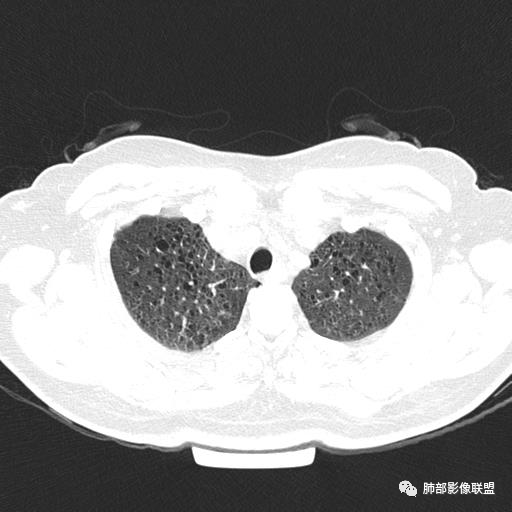

双肺弥漫囊腔,累及肋膈角,囊腔形态相对规则单一。

CT平扫示双肺弥漫分布大小不等囊状薄壁透光区,无内、中、外带分布差异,间质稍示增厚。拟LAM

双肺弥漫大小不一薄壁含气囊腔,囊间肺组织正常,正常肺背景,肺尖肺底受累;青年女性,气喘,支持LAM

CT表现:双肺弥漫大小不等的薄壁囊腔,囊壁<2mm,外形规则,血管影多位于囊腔周围,囊腔之间肺组织正常,随着疾病进展到晚期,囊腔变大、增多,不可胜数,囊腔可融合成较大的囊,与肺气肿相似,形成间质性肺纤维化。部分病例可出现结节影。